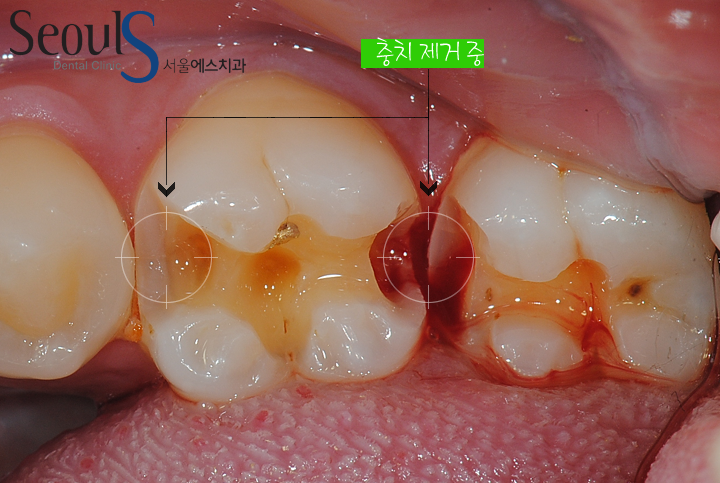

치료를 위해 금을 제거했습니다

화살표로 표시한 부분을 보시면 검게 충치가 진행되고 있습니다

진행되고 있는 충치를 깨끗히 제거하고 인레이 제작 후 때울 예정입니다

충치를 제거하고 있습니다

맨 끝 어금니도 충치가 진행되고 있어서 제거하는 모습입니다

사이 충치로

일반적으로 사이 충치는 치아 사이에 음식물이 꼈을 때

음식물을 중심으로 양쪽 치아에 동시에 진행되는 경우가 많습니다